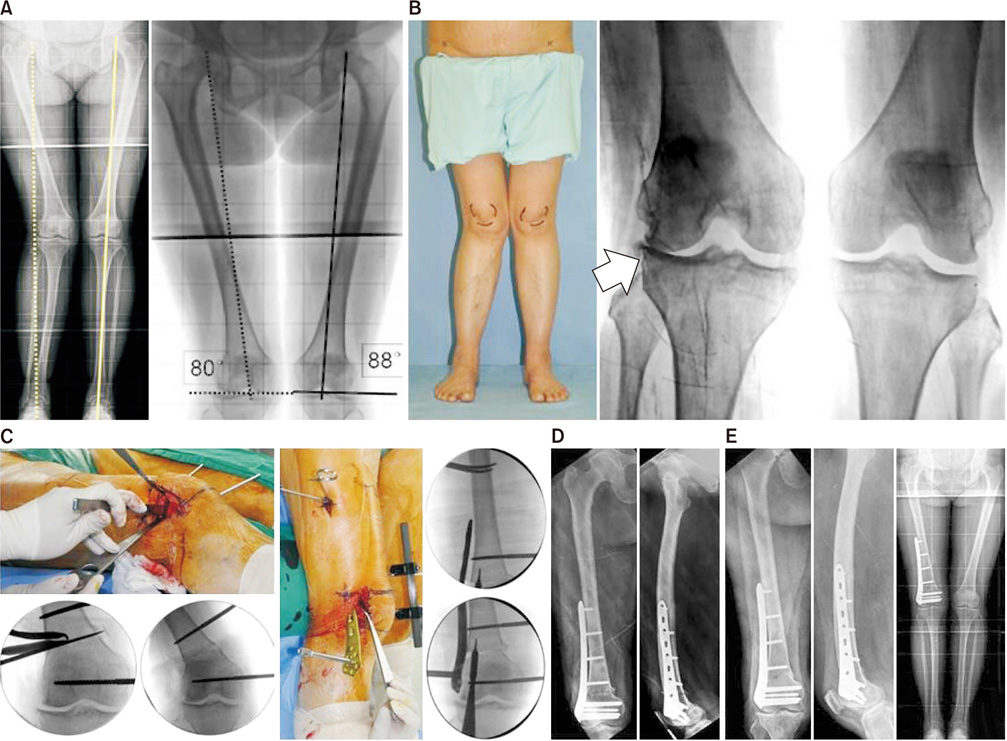

(A) Valgus deformity was observed in the right distal femur as trauma at the growing age. The mechanical axis was deviated to the lateral side by more than moderately. The mechanical lateral distal femoral angle was 88 degrees on the left side and 80 degrees on the right side. (B) On weight-bearing radiographs, arthritic changes were noted in the lateral part of the knee (arrow), and the patient complained of pain during gait. (C) Osteotomy was performed through the lateral parapatellar approach. (D) The minimally invasive lateral plating was performed with a lateral open wedge osteotomy. (E) After a 3-year follow-up, the femoral alignment was recovered and the union was completed.

Fig. 2 (A) Valgus deformity was observed in the right distal femur as trauma at the growing age. The mechanical axis was deviated to the lateral side by more than moderately. The mechanical lateral distal femoral angle was 88 degrees on the left side and 80 degrees on the right side. (B) On weight-bearing radiographs, arthritic changes were noted in the lateral part of the knee (arrow), and the patient complained of pain during gait. (C) Osteotomy was performed through the lateral parapatellar approach. (D) The minimally invasive lateral plating was performed with a lateral open wedge osteotomy. (E) After a 3-year follow-up, the femoral alignment was recovered and the union was completed.